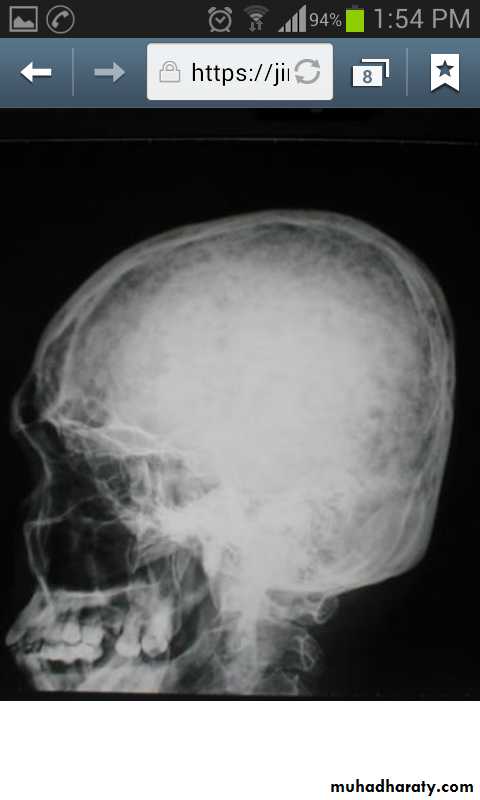

Skeletal X-rays:

Normal in early disease

Demineralization

Subperiosteal erosions and terminal resorption of phalanges

Salt and paper appearance on lat. skull x-ray

Osteopenia and osteoporosis by DEXA